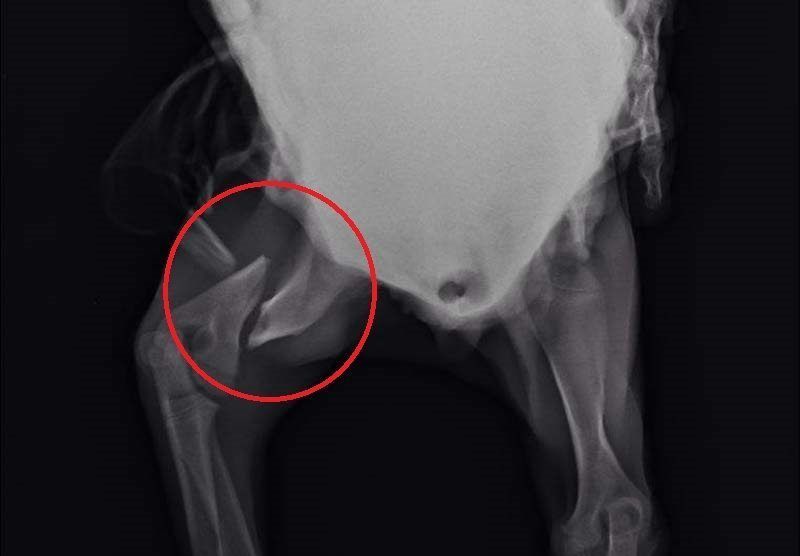

Το κουταβάκι που βλέπετε στις φωτογραφίες εντοπίστηκε χθες στο Άκτιο να κλαίει από τους πόνους κοντά στα διόδια της υποθαλάσσιας σήραγγας καθώς όπως αποδείχτηκε έχει σπασμένα τα δύο πόδια του ενώ είναι χτυπημένο και στην κοιλιά. Το πως τραυματίστηκε το ζώο παραμένει άγνωστο αν και σύμφωνα με τον κτηνίατρο Νίκο Ρώσσο, που το εξέτασε, κάποιος είναι πολύ πιθανό να το το κλώτσησε.

Η Δώρα Τσάτση μέλος του σωματείου «Παρέμβαση για τα Ζώα - Πρέβεζα» εξήγησε στο www.zoosos.gr ότι ο κ. Ρώσσος τους είπε πως είναι απίθανο το κουταβάκι, που ζυγίζει μόλις τέσσερα κιλά, να χτυπήθηκε από όχημα καθώς δεν έχει σημάδια και αυτά τα τραύματα προκαλούνται μόνο από κλωτσιά.

Εξαιτίας του νεαρού της ηλικίας του κουταβιού δεν θα γίνουν όλες οι επεμβάσεις ταυτόχρονα. Αρχικά θα χειρουργηθεί στην κοιλιά και στην συνέχεια θα ακολουθήσουν οι επεμβάσεις στο πίσω πόδι του που έχει σπάσει σε δύο σημεία και στη συνέχεια στο μπροστινό.